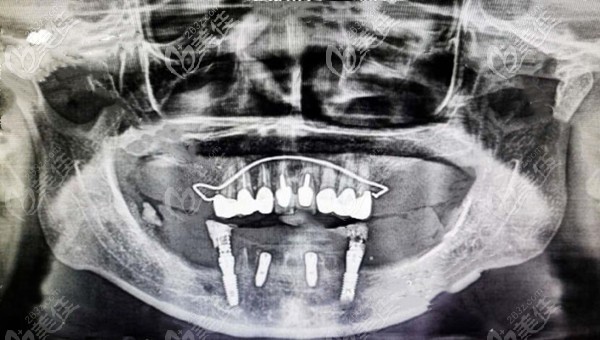

患者牙齒情況:男,60歲,因牙周病導致下頜大部分缺損,長達十余年,咀嚼困難。

治療計劃:allon4半口種植牙修復,馬龍橋+氧化鋯全瓷

下頜半口馬龍橋修復效果圖▼